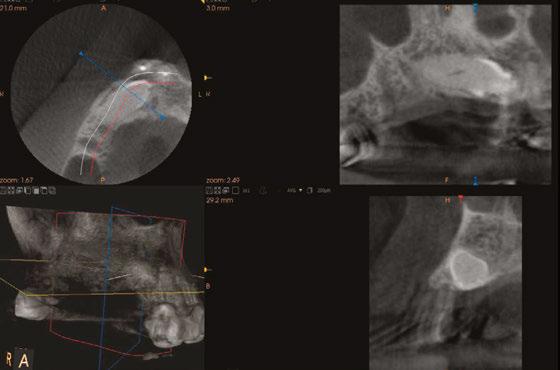

Mr. Z has a skeletal Class III malocclusion. He has never received orthodontic treatment. The CBCT shows tooth No. 6 is present but horizontally impacted (Figure 4).

Based on age of patient, health history, and presence of the impacted canine, the patient was sent to an oral surgeon for evaluation. The initial consultation asked the surgeon to consider removal of impacted tooth No. 6 and placement of bone graft as a prelude to restoring site 2-7 with an implant-supported fixed bridge (Figures

Close inspection of the CBCT shows tooth No. 6 is ankylosed. The oral surgeon indicated extraction of tooth No. 6 would require block resection of bone with the tooth. The resulting defect would have required extensive bone grafting

added time and cost to this case.

Figures 7 and 8: Healing abutments in place Figure 4: Pretreatment panoramic x-ray. Note position of maxillary right canine Figures 5 and 6: Pretreatment CBCT scan with treatment planning software. Virtual implant placement at site 10 shows thin buccal bone. Buccal bone graft was provided at time of surgery Figures 9 and 10: Porcelain-on-metal framework ready for delivery

2. Paton G, Fuss J, Goss AN. The transmandibular implant: a 5- and 15-year single-center study. J Oral Maxillofac Figure 14. Post implant placement. This CBCT shows implant at site 10 through the impacted canine. Implant at site 3 was placed right against the sinus floor Figures 13A and 13B: 13A. Trans-mandibular dental implants. 13B. Subperiosteal implants Figure 11: Surgical site on day of surgery Figure 12: Implant placement of tooth No. 7 with buccal bone graft